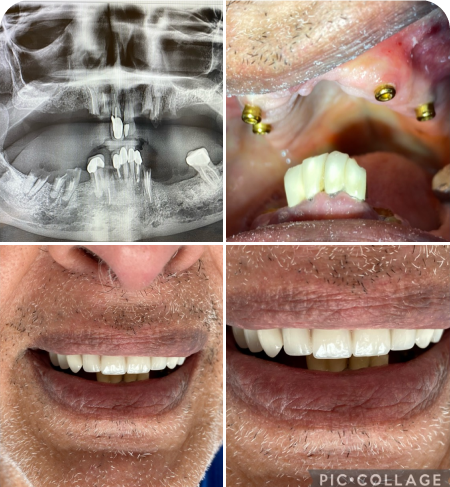

Implants

At Tooth, we provide all General Dentistry services, and 99 percent of all other Dental specialty services under one roof. Our goal is to provide all our patients with caring, supportive dental visits so you can feel loose and relaxed like we are family. We strive to stand out as a Trusted Practice that gives back to our community and the Greater Sacramento Area and provides the highest quality of Dentistry backed by Dr. Badyal’s guarantee on all Procedures.

5,000+

Placed